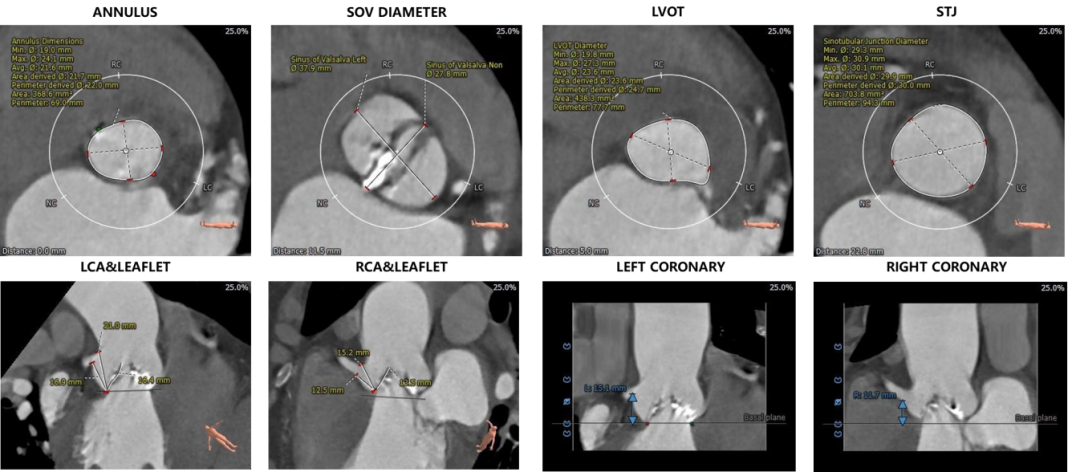

1.主动脉瓣瓣环周长69.0mm,平均周长径22.0mm。

2.Type0型二叶式主动脉瓣,左右冠不同窦,重度钙化,钙化分布欠均匀,右冠瓣尤甚,主要分布于瓣叶边缘及管壁附着缘,瓣叶增生肥厚。

3.左右冠开口高度较高,未见明显钙化,右冠瓣叶长度>右冠开口到右冠瓣叶附着缘距离。

4.瓦氏窦内径尚可,窦管交界内径可,升主动脉无扩张,LVOT内径大于瓣环,呈火山口状。

5.左室腔内径可,心室壁不厚。主动脉瓣环与水平面夹角54°,主动脉弓部夹角与弓距可。

主动脉根部评估:

根部概览

瓣环上解剖结构评估